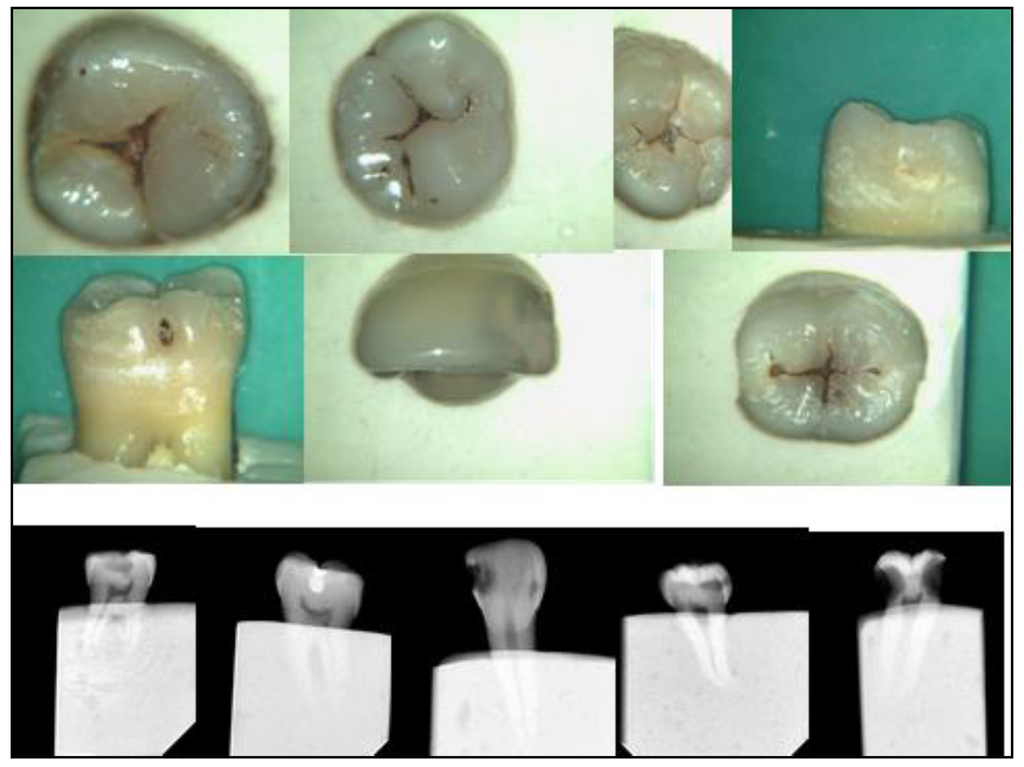

The next step was to start selecting and collecting appropriate extracted teeth with various stages of caries lesions. They were cleaned and their digital images taken with the Camsight digital surgical scope camera (Figure 2). Photographs were also taken of carious teeth seen clinically in patients’ mouths (Figure 3). That began the creation of a collection of training resources and tools at IMU.

Figure 2. Camsight digital images of extracted teeth depicting different ICDAS codes with some radiographs.

At the same time, a ‘Reference Set’ of carious extracted teeth exhibiting an adequate number of surfaces with the different ICDAS codes was gradually and carefully examined, graded and collected over a period of several months (Figure 4). Radiographs were taken of each tooth to eliminate or confirm the presence of deeper carious lesions (Figure 2). Numerous discussion meetings took place so that the committee could come to an agreement on the ICDAS code given for each of the caries lesions on the surfaces of these teeth.